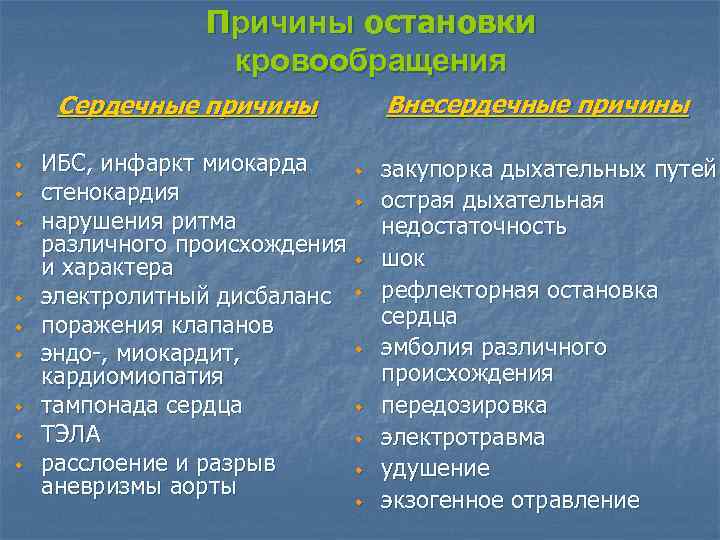

Причины остановки кровообращения Внесердечные причины Сердечные причины w w w w w ИБС, инфаркт миокарда w стенокардия w нарушения ритма различного происхождения w и характера электролитный дисбаланс w поражения клапанов w эндо-, миокардит, кардиомиопатия w тампонада сердца ТЭЛА w расслоение и разрыв w аневризмы аорты w закупорка дыхательных путей острая дыхательная недостаточность шок рефлекторная остановка сердца эмболия различного происхождения передозировка электротравма удушение экзогенное отравление